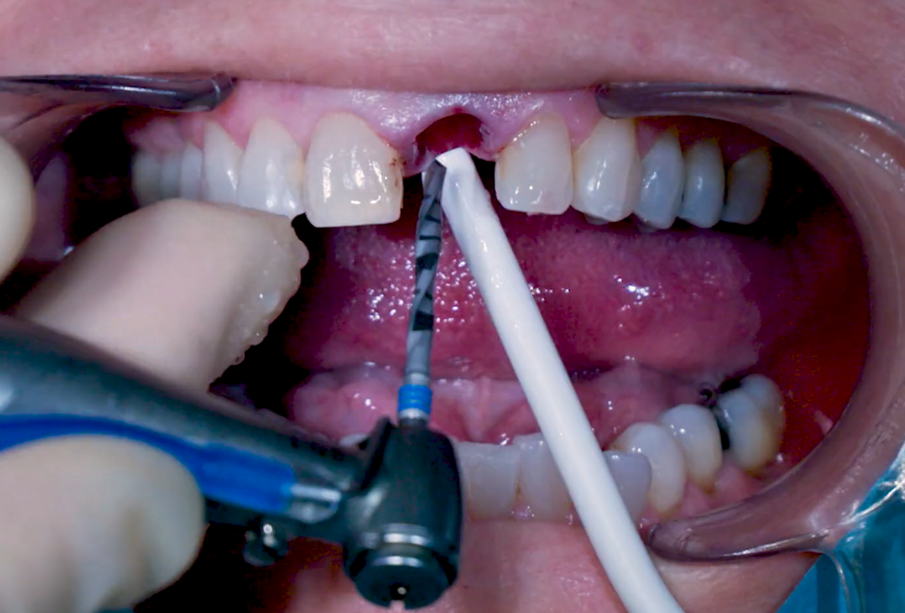

La fresa preliminare da Ø 2,2 mm è stata utilizzata sulla rispettiva lunghezza prevista dall’impianto, seguita da un perno di allineamento per controllare l’orientamento in 3D (Figg. 6, 7). Le frese da Ø 2,8 mm e Ø 3,2 mm sono state utilizzate per completare l’osteotomia (Fig. 8). Il sito è stato quindi opportunamente sondato per valutare la possibile perforazione della parete. Un impianto 4×14 mm è stato posizionato, a partire dalla maniglia chirurgica che coinvolge la parte apicale dell’impianto, seguendo lo stesso orientamento dell’ago perforatore e correggendo la direzione dell’impianto mentre si spostava all’interno dell’osteotomia (Figg. 9, 10). La stabilità primaria (45 Ncm) è stata raggiunta nella posizione finale.

Fig. 7_Conferma 3D con perno di allineamento Ø 2,2 mm.

Fig. 8_Osteotomia con trapano Ø 3,2 mm.